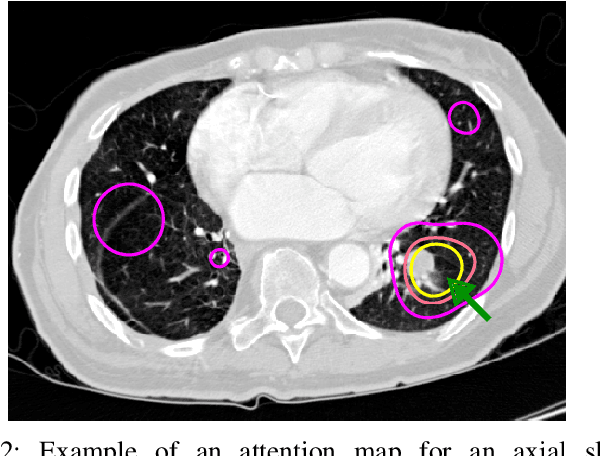

Abstract:Early diagnosis of lung cancer via computed tomography can significantly reduce the morbidity and mortality rates associated with the pathology. However, search lung nodules is a high complexity task, which affects the success of screening programs. Whilst computer-aided detection systems can be used as second observers, they may bias radiologists and introduce significant time overheads. With this in mind, this study assesses the potential of using gaze information for integrating automatic detection systems in the clinical practice. For that purpose, 4 radiologists were asked to annotate 20 scans from a public dataset while being monitored by an eye tracker device and an automatic lung nodule detection system was developed. Our results show that radiologists follow a similar search routine and tend to have lower fixation periods in regions where finding errors occur. The overall detection sensitivity of the specialists was 0.67$\pm$0.07, whereas the system achieved 0.69. Combining the annotations of one radiologist with the automatic system significantly improves the detection performance to similar levels of two annotators. Likewise, combining the findings of radiologist with the detection algorithm only for low fixation regions still significantly improves the detection sensitivity without increasing the number of false-positives. The combination of the automatic system with the gaze information allows to mitigate possible errors of the radiologist without some of the issues usually associated with automatic detection system.